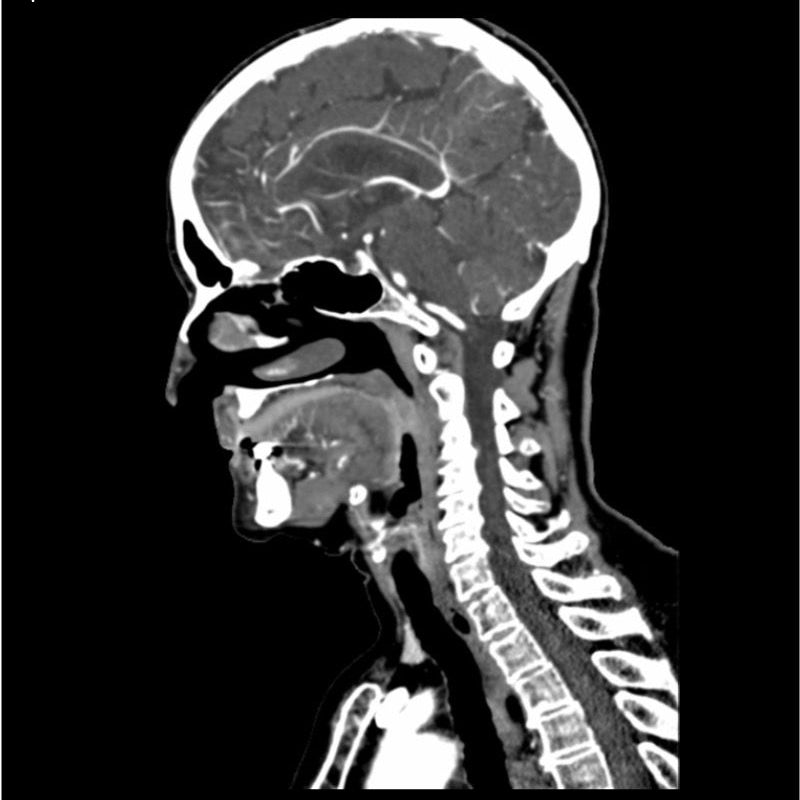

This phantom simulates a contrast medium enhanced head in arterial phase (CT angiography). The neck and upper thorax are included up to the aortic arch and the fifth thoracic vertebra. The vertex is included until approximately 0.5 cm below skin level. The thoracic phantom section excludes shoulder and back parts that are typically not part of CTA examinations. The interncal carotid artery has calcifications on both sides with moderate stenosis on the right side. Otherwise, the phantom has no significant vascular pathologies.

The phantom can be used in CT (including CBCT) to evaluate and optimize CTA imaging performance and post-processing applications such as vessel segmentation, including AI-enabled applications. It is also nicely suited for training purposes. The phantom provides a detailed and realistic simulation of vascular structures, soft and bone tissue, including small details such as lymph nodes. Air voids are filled with a cellulose-polymer composite of approx. -160 HU.

Realistic simulation of head and neck vessels up to the aortic arch, bone and soft tissues.

Calcifications of the internal carotid artery at the carotid bifurcation on both sides with mild stenosis on the right side.